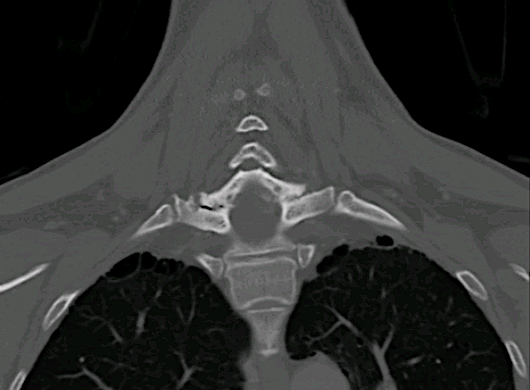

Se solicitó un TC observando signos de espondilosis avanzada C5-C6-C7 y ausencia de infiltración ósea.

En la imagen coronal se aprecia relación íntima de la lesión con la faceta C7-Th1 que nos hizo sospechar el diagnóstic